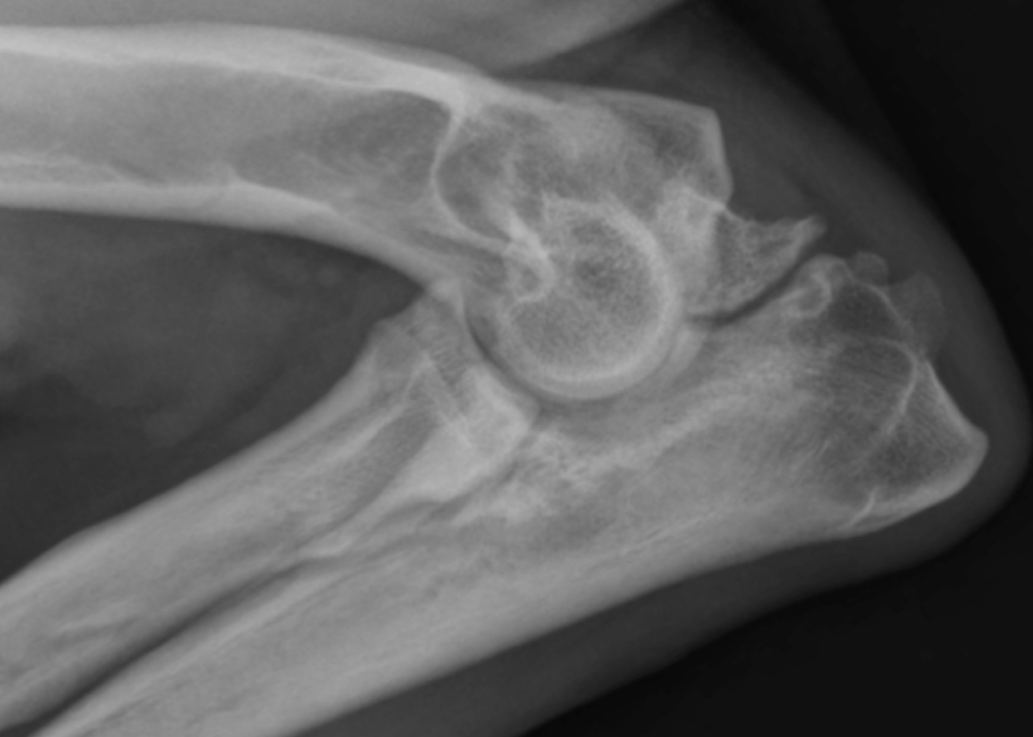

Cette carte de concepts créée avec IHMC CmapTools traite de: Non-Union du processus anconné-Camille, Examen radiographique qui consiste 2 radiographies de profil: - coude en flexion maximale - coude en extension, Douleur lors de l'extension du coude Pouvant évoluer en Inconfort si le processus anconné se libére dans l'articulation, Insatbilité du coude entraîne Inconfort si le processus anconné se libére dans l'articulation, Non Union Du Processus Anconné est provoqué Une non-fermeture de la plaque de croissance qui empêche la fusion du processus anconné à l'ulna(à 4-5 mois)., Traitement chirurgical basé sur l'élimination du fragment du processus anconé libre, Une non-fermeture de la plaque de croissance qui empêche la fusion du processus anconné à l'ulna(à 4-5 mois). dû à l'hérédité mais aussi d'autres facteurs., Non Union Du Processus Anconné entraine Instabilité du coude entrainant des douleurs et des boiteries, Certains chiens de grandes races à croissance rapide avec un ratio de 2:1 pour les mâles dont par ordre décroissant La principale: Berger allemand (77%) Incidence: 18%, Traitement chirurgical basé sur l'ostéotomie ou ostectomie de l'ulna avec ou sans fixation du processus anconné, Traitement médical en Evitant les jeux, Traitement médical en Privilégiant la nage et la marche en laisse, Epanchement synovial Pouvant évoluer en Dégénerescence arthrosique, Non Union Du Processus Anconné est traité Soit par: o o, Désequilibre en: o Calcium o Phosphore o Vitamine D Non-union du processus anconé, Traitement chirurgical basé sur le réattachement chirurgical du processus anconé, Insatbilité du coude entraîne Inflammation articulaire, La génétique: o Multigènique o Gènes non identifiés o Morphologie des grands chiens Qui entraîne Soit: o Croissance asynchrone du radius et de l'ulna qui est trop court o Défaut d'ouverture de l'incisure trochléaire, Certains chiens de grandes races à croissance rapide avec un ratio de 2:1 pour les mâles dont par ordre décroissant Saint-Bernard, Traitement médical en Surveillant le poids, Certains chiens de grandes races à croissance rapide avec un ratio de 2:1 pour les mâles dont par ordre décroissant Dogue allemand